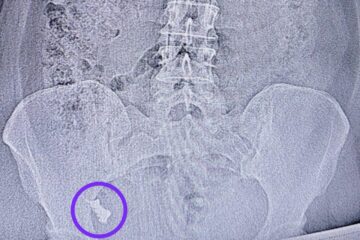

Медики в Татарстане по особой методике спасли суставы женщине с некрозом 17:43 | 27-03-2026 Общество Почти год 45-летняя женщина мучилась от болей в паху. Прошла терапевта, гинеколога, хирурга и в конце-концов дошла до травматолога. Как оказалось, у женщины асептический некроз обеих головок тазобедренных костей, что является прямым показанием к эндопротезированию, сообщает РКБ Республики Татарстан. Заведующий... Инфаркт, тампонада, схлопнувшиеся легкие: как врачи РКБ Татарстана вытащили пациентку с того света 07:54 | 27-03-2026 Общество Инфаркт, остановка сердца, тампонада, кома и схлопнувшиеся легкие — эта история о том, как врачи Республиканской клинической больницы Татарстана три раза подряд спасли 63-летнюю пациентку. Об этом сообщает пресс-служба больницы. Женщина поступила в РКБ Татарстана 6 февраля в 22:00 с... Медики РКБ Татарстана спасли беременную женщину, у которой произошел разрыв опухоли в почке 17:04 | 11-03-2026 В Республике Татарстан врачи Республиканской клинической больницы спасли беременную женщину, у которой случился разрыв опухоли почки. Об этом сообщает пресс-служба клиники. Женщина была на 22-й неделе беременности. Внезапно на работе у нее закололо в животе, а потом начались боли, от... Скончался главный комбустиолог Татарстана Радик Новиков 09:26 | 05-03-2026 Общество На 60-м году жизни скончался главный внештатный комбустиолог Министерства здравоохранения Республики Татарстан, заведующий ожоговым отделением РКБ Радик Новиков. Об этом сообщила пресс-служба больницы. Радик Новиков посвятил медицине почти 30 лет. Свой профессиональный путь он начал в 1996 году врачом-хирургом в... За месяц в РКБ попали 17 человек, пострадавших при уборке снега с крыш 20:34 | 26-02-2026 Общество За последний месяц в Республиканскую клиническую больницу попали 17 человек, которые пострадали при уборке снега с крыш. Об этом сообщили в самом медучреждении. Большинство пациентов получили травмы, когда чистили кровли частных домов или снимали новогодние украшения. Врачи диагностировали переломы позвоночника,... Разрослась на половину лица: врачи РКБ РТ удалили пациенту гигантскую липому – фото 14:43 | 12-02-2026 Происшествия Липома размером с ладонь выросла на лице у жителя Республики Татарстан за месяц, сообщает пресс-служба РКБ. 63-летний мужчина обратил внимание на маленькое образование около года назад, но за последний месяц опухоль резко выросла. Из-за этого он пошел на обследование. В... Девочку с травмой сердца спасли с помощью вертолёта из Татарстана 22:57 | 09-02-2026 Общество В Приморском крае состоялась экстренная медицинская эвакуация тяжело травмированной девочки с использованием санитарной авиации. Об этом сообщает пресс-служба «Ростеха». Ребёнок получила серьёзную травму в области сердца и была доставлена в больницу села Черниговка, где медики провели операцию и стабилизировали её... Огромный зоб едва не задушил жительницу Альметьевска 11:03 | 02-02-2026 Общество Врачи Республиканской клинической больницы Татарстана совершили почти невозможное, избавив 71-летнюю жительницу Альметьевска от патологии, с которой она жила почти сорок лет. Все эти годы женщина не решалась на хирургическое вмешательство из-за сильного страха. Об этом сообщает пресс-служба РКБ. Пациентка долгие... Подрезали аппетит: врачи РКБ впервые без разрезов ушили желудок пациентки весом более 170 кг 08:00 | 24-01-2026 Общество «Была в состоянии, когда казалось, что дальше остается уже просто доживать свое» 52-летняя Лариса Калашникова большую часть жизни страдала из-за лишнего веса. Не могла ходить без помощи, долго стоять, выполнять казалось бы обычные домашние дела. Ее постоянно мучила одышка. Пятнадцать... Казанские хирурги вернули мужчине зрение, восстановив орбиту глаза с помощью реберного хряща 13:58 | 30-12-2025 Общество Орбиту глаза после травмы восстановили мужчине в Республиканской Клинической больнице Татарстана с помощью реберного хряща, сообщает телеграм-канал больницы. 6 декабря житель Тетюшского района получил травму глаза. Врачи оказали ему первую помощь в ЦРБ и отправили на больничный. Через две недели,... Первые в ПФО: врачи Татарстана с помощью протеза восстановили локоть бойцу СВО 15:28 | 25-12-2025 Общество Одну из редких в травматологии операций – эндопротезирование локтевого сустава – выполнили впервые в ПФО. Провели ее в РКБ Татарстана, сообщили в пресс-службе лечебного учреждения. Операция требовалась 23-летнему участнику СВО Василию Сундерову. В бою под Авдеевкой его локоть навылет пробил... В Казани одобрили проект нового центра трансплантации 10:36 | 23-12-2025 Общество Проект строительства центра трансплантации в столице Республики Татарстан одобрили в управлении государственной экспертизы и ценообразования РТ по строительству и архитектуре. Такая информация появилась на сайте единого государственного реестра заключений. Заказчиком является Главстрой Республики Татарстан, а сам проект подготовил ГУП «Татинвестгражданпроект».... Татарстанские врачи извлекли из бронха пациента баранью кость 15:35 | 22-12-2025 Общество Баранью кость извлекли из бронха у пациента врачи РКБ Казани. О необычном случае рассказала пресс-служба лечебного учреждения. Торакальный хирург Виктор Напалков осторожно достал кость. После этого в течение нескольких дней пациента наблюдали в отделении. В результате его отпустили домой. «Впереди... Квашенная капуста-убийца: бабушка из РТ едва не погибла из-за любимого лакомства 14:29 | 22-11-2025 Происшествия В Республиканскую клиническую больницу ночью поступила 76-летняя пациентка, которая подавилась квашеной капустой. Женщине срочно потребовалась помощь специалистов, и два врача выехали в клинику, чтобы извлечь застрявший кусок пищи, пишут в пресс-службе РКБ. Эндоскопист-бронхолог Фанис Ришатович Нурмиев и торакальный хирург Артем... Челнинцу пришили руку к животу, чтобы вырастить новый палец взамен отрезанного 15:15 | 01-11-2025 Общество Новый палец на руке вырастили 57-летнему жителю Набережных Челнов микрохирурги РКБ Татарстана. О необычном случае рассказали в пресс-службе лечебного учреждения Казани. Мужчина случайно отрезал себе большой палец левой руки болгаркой, когда ремонтировал беседку на даче. Местные врачи оказали медпомощь, зашили... Пуля в позвоночнике: врачи Казани спасли парня, выстрелившего себе в шею из ружья 13:55 | 31-10-2025 Происшествия Врачи РКБ Казани спасли 25-летнего жителя Зеленодолького района, который нечаянно выстрелил себе в шею из пневматического ружья. О необычном случае сообщили в медучреждении. Парень рассказал, что разбирал ружье и не заметил, как сработал механизм – он лишь услышал выстрел и... В Татарстане только 10% пациентов дожидаются пересадки печени 09:46 | 30-10-2025 Общество В Татарстане с начала года пересадили печень 54 пациентам. Об этом на III Всероссийском гастрофоруме сообщила гастроэнтеролог, заведующая гастроэнтерологическим отделением РКБ Альфия Одинцова. Всего с 2019 года в республике провели 219 операции по пересадки печени. Врач добавила, что ежегодно лишь... Врачи РКБ Татарстана поставили на ноги 104-летнюю бабушку, сломавшую бедренную кость 09:56 | 22-10-2025 Общество Травматологи-ортопеды и анестезиологи-реаниматологи РКБ Татарстана поставили на ноги 104-летнюю бабушку, сломавшую бедренную кость. О случае рассказали в лечебном учреждении. Сахибя получила перелом при падении. На помощь ей пришли специалисты РКБ. Пожилую женщину сутки готовили к операции. после травматолог-ортопед смог поставить... Жительница Казани едва не погибла, проглотив часть зубного протеза 16:13 | 13-10-2025 Происшествия В Республиканской клинической больнице Татарстана врачи-эндоскописты извлекли зубной протез из кишечника 50-летней жительницы Казани, который находился в организме пациентки в течение недели. Об этом сообщила пресс-служба министерства здравоохранения Республики Татарстан. Пациентка поступила в хирургическое отделение №1 РКБ через неделю после... Видео: в Казани у РКБ мощная авария, один из автомобилей разбился об отбойник 21:01 | 11-10-2025 Происшествия В Казани недавно произошла серьезная авария недалеко от РКБ. Соответствующие кадры появились в местных telegram-каналах. На видео видно, что как минимум два автомобиля получили серьезные повреждения в результате, вероятно, лобового столкновения. Причем один из них влетел в итоге в отбойник,... «Татарину» с дырой в черепе врачи Казани восстановили лоб, задействовав принтер 12:15 | 08-10-2025 Общество Врачи РКБ в Казани восстановили лоб после ранения 35-летнему бойцу СВО с позывным «Татарин», используя 3D-принтер. О случае рассказали в лечебном учреждении. Мужчина ушел добровольцем в зону спецоперации в феврале 2024 года. Перед этим он специально отучился на снайпера. Летом... Осколок между аортой и позвоночником: в Казани провели редкую операцию бойцу СВО 13:47 | 03-10-2025 Общество Редкую и сложную операцию провели врачи РКБ Татарстана 22-летнему бойцу СВО Ильсафу Ахметшину с осколком между аортой и позвоночником. О случае рассказали в лечебном учреждении. Военнослужащий получил ранение под Брянском. Сначала его госпитализировали в ближайшую клинику, где оказали всю необходимую... «Лапонька, не суетись»: в Казани простятся с организатором гематологической службы РТ 14:45 | 25-08-2025 Общество Церемония прощания с организатором гематологической службы Татарстана Арысланом Ахмадеевым, который скончался на 70-м году жизни, состоится в в патологоанатомическом отделении РКБ Казани 26 августа. Начало в 10:00 . Похороны пройдут на кладбище в поселке «Мирный» в 11:30. Об этом сообщили... Чудом осталась жива: врачи РКБ РТ спасли молодую маму с некрозом матки после кесарево 08:30 | 07-07-2025 Общество В Республиканской клинической больнице Казани врачи спасли 35-летнюю женщину, у которой после кесарева сечения развилось тяжелое осложнение. Об этом сообщили в пресс-службе медицинского учреждения. 29 мая беременную госпитализировали в роддом по месту жительства. 3 июня, после начала родовой деятельности и... 1 2 3 4 5 … 12 » Студия ЯЛ - создание сайтов для СМИ